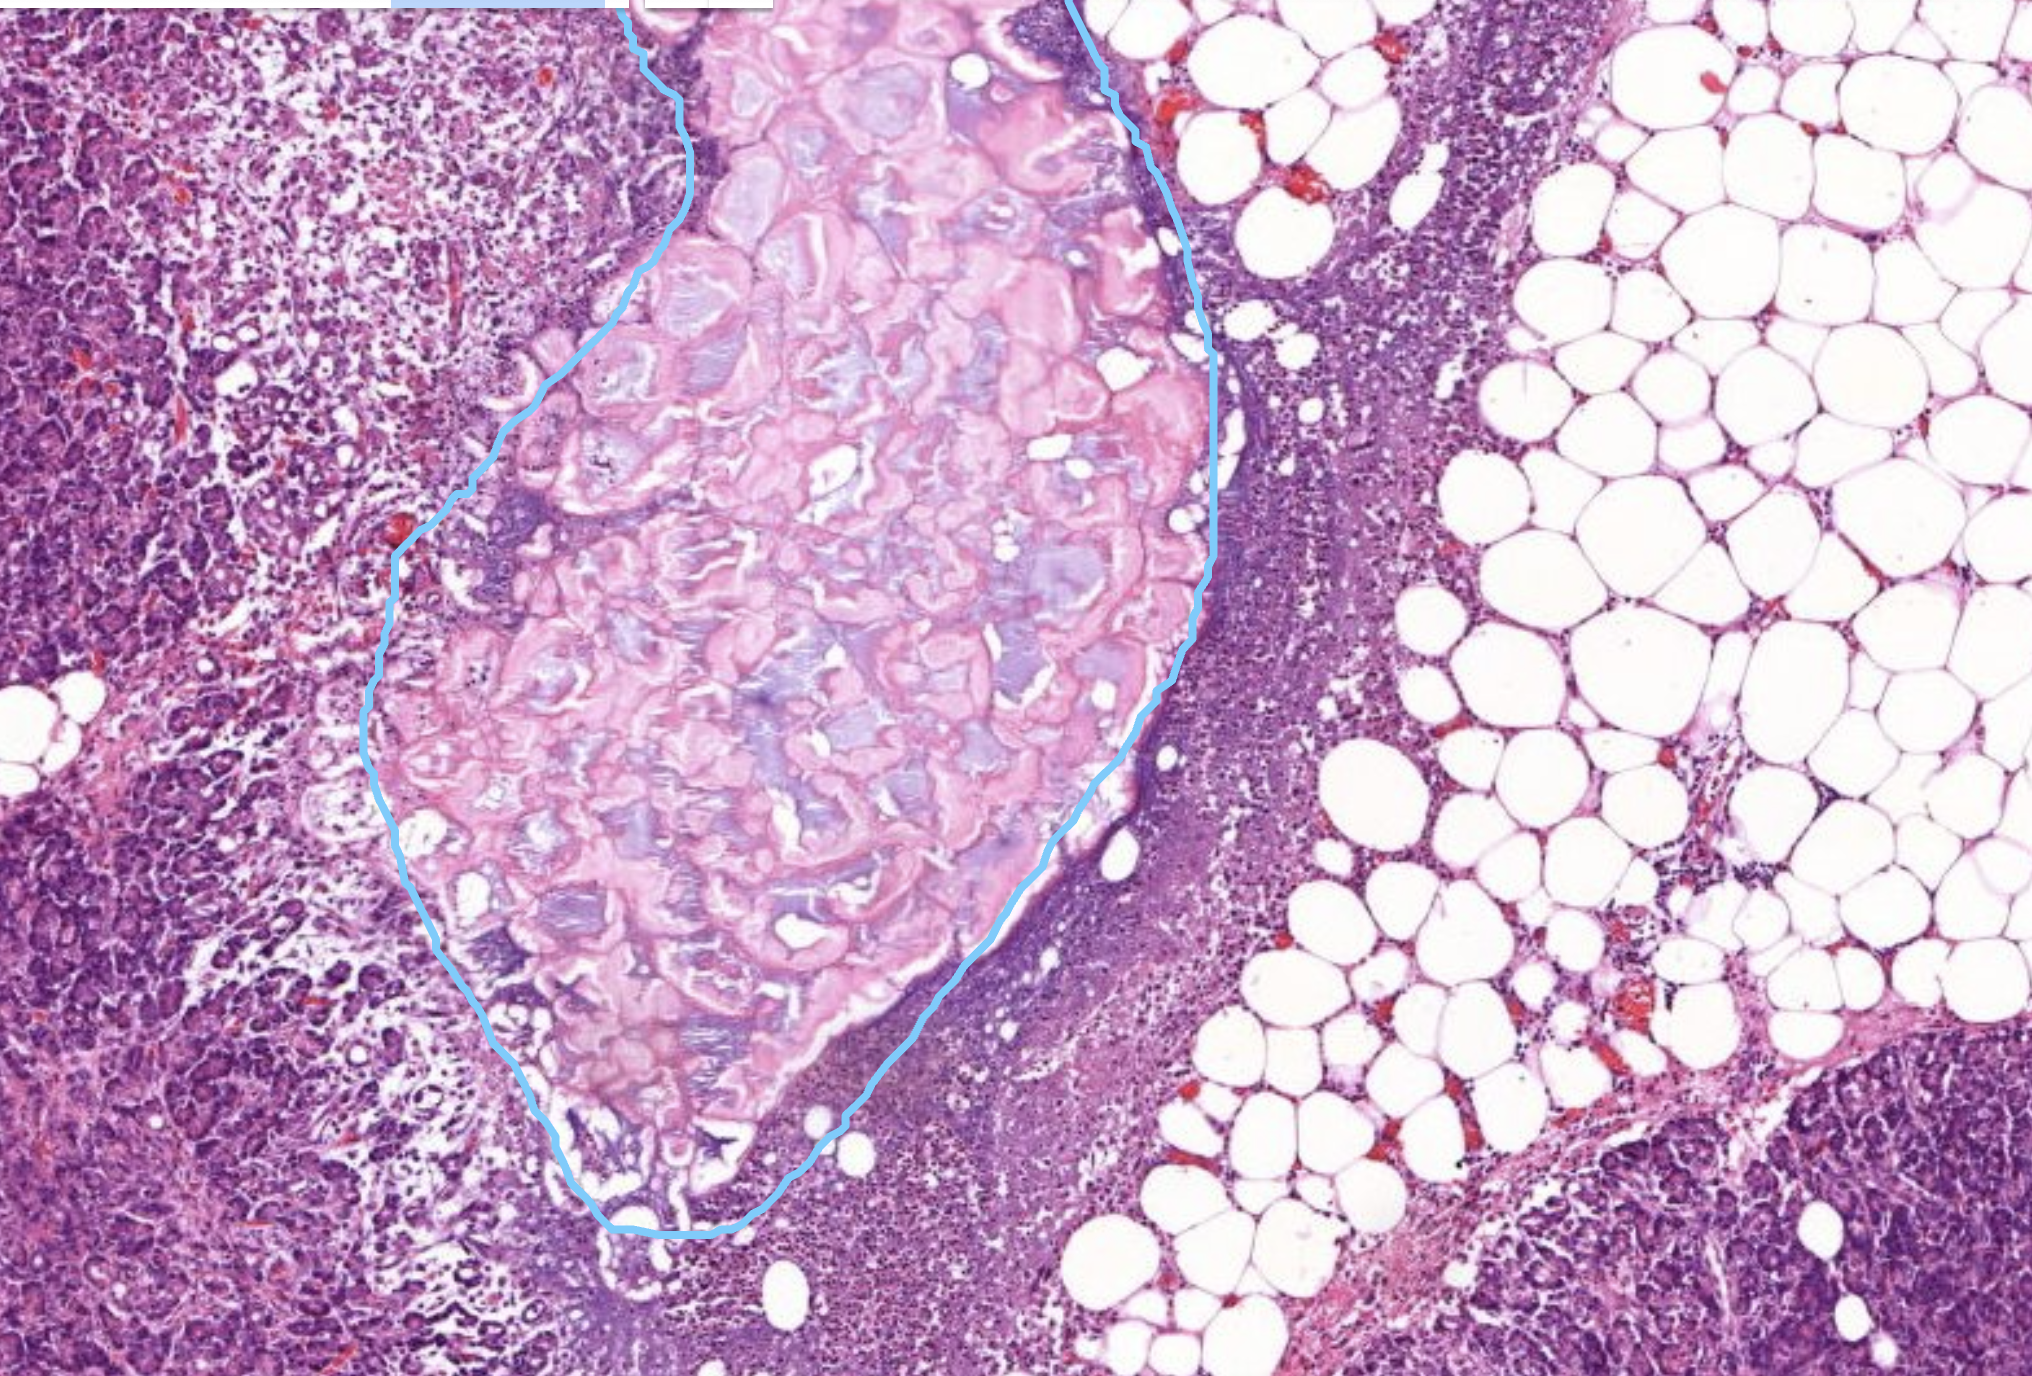

41) Z698 Pankreatitis - Beschreiben Sie die histopathologischen Merkmale.

Zu sehen ist eine Pankreatitis. Hier soll es um besonders um die Fettegwebsnekrose gehen. Eine Lipolytische Fettgewebsnekrose, der Pankreas verdaut sich quasi selber, denn bei der Entzündung des Pankreas werden die Pankreasenzyme die sonst in den Dünndarm geleitet werden

Hier betrifft die Nekrose erstmal nur die Fettzellen, würde aber auch auf das Paarenchym übergehen. Es zeigt sich außerdem Lymphozytäres infiltrat im sinne von neutrophilen Granulaten Histopathologisches Bild: Prostatahyperplasie mit knotiger Architektur Trypsinische Parenchymnekrose Das aktivierte Trypsin führt zur Proteolyse (Eiweißspaltung) des Pankreasparenchyms (der Drüsenzellen, Gefäßwände usw.). Diese Zerstörung des Pankreasgewebes nennt man tryptische Parenchymnekrose. Histopathologisches Bild: Prostatahyperplasie mit knotiger Architektur